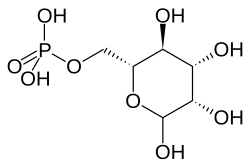

The wild-type PPT1 is a 306-amino acid polypeptide that is typically targeted for transport into lysosomes by the mannose 6-phosphate (M6P) receptor-mediated pathway.[6][20] Here, the protein appears to function in removing palmitate residues by cleaving thioester linkages in s-acylated (or palmitoylated) proteins, encouraging their breakdown.[6][7] Defective polypeptides, however, are unable to exit the endoplasmic reticulum (ER), most likely due to misfolding; further analyses of this pathway could serve to categorize INCL among lysosomal enzyme deficiencies. The human PPT gene shows 91% similarity to bovine PPT and 85% similarity to rat PPT; these data indicate that the PPT gene is highly conserved and likely plays a vital role in cell metabolism.[6] In addition, buildup of defective PPT1 in the ER has been shown to cause the increased release of Ca2+. This homeostasis-altering event leads to increased mitochondrial membrane permeability and subsequent activation of caspase-9, eventually leading to an accumulation of cleft and uncleft poly(ADP-ribose) polymerase and eventual apoptosis.[7]